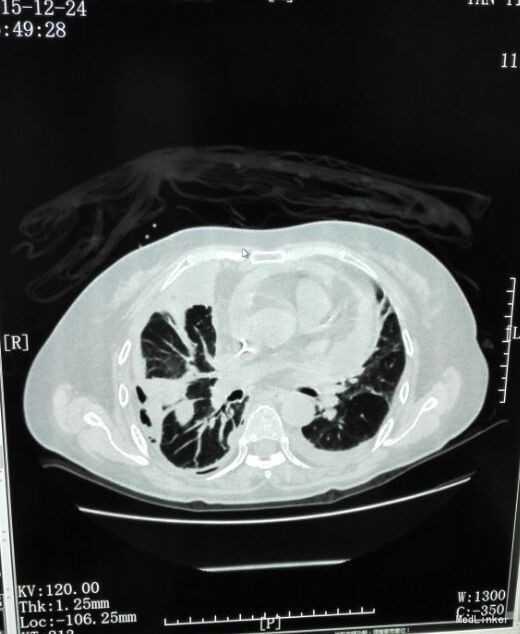

患者入院后予“美洛西林舒巴坦”抗感染,当天晚上出现明显气促,伴右后下背痛,无明显发热,当时复查胸片示: 1、双下肺炎症、双侧胸腔积液,同2015.12.13前片比较,考虑右侧胸腔积液明显增多,部分包裹,建议CT进一步检查。血气分析未见明显异常,2015-12-14 复查急诊血常规:白细胞计数 24.290(10E9/L)↑,淋巴细胞计数 0.750(10E9/L)↓,中性粒细胞比例 0.930↑,血红蛋白浓度 104.000(g/L)↓,中性粒细胞计数 22.590(10E9/L)↑,红细胞计数 3.500(10E12/L)↓,血小板计数 466.000(10E9/L)↑,单核细胞计数 0.920(10E9/L)↑;急诊肾功(三项):尿素氮 8.450(mmol/L)↑;急诊电解质(K/Na/Cl):钠 128.700(mmol/L)↓,氯 87.100(mmol/L)↓; 2015-12-14胸部及上腹部CT平扫+增强示:1、两中下肺多发炎症,部分萎陷。建议治疗后复查。2、双侧胸腔积液(右著);心包少量积液。3、结合病史,右输尿管术改变;右侧双J管置入术后。右肾、输尿管上段扩张、积水,右肾周感染并少许积气;左肾结石。4、脂肪肝。5、胆、脾、胰未见异常。因CT提示肺部大片实变,包裹性积液(量少),考虑重症肺炎可能,于2015-12-14将抗生素升级为“亚胺培南西司他丁 1.0 q8h、万古霉素 50万U q12h、伏立康唑 0.2 q12h”三联,同时予“甲强龙”抗炎等治疗。经治疗,患者气促症状逐渐缓解,咳嗽、咳痰、右后背疼痛好转,无发热,精神、胃纳较前改善。因B超定位下胸水量少,暂未予胸穿。2015-12-17复查胸部+上腹部CT平扫示:1、双中下肺炎炎症较前吸收好转,右侧胸腔积液较前略有减少,左侧胸腔积液现已基本吸收。2、胸、腹主动脉粥样硬化;心包少量积液(大致同前)。纵膈内临界肿大淋巴结。3、右输尿管术改变;右肾、输尿管上段扩张、积水,右肾周慢性感染(原右肾周积气消失);左肾结石。4、轻度脂肪肝。少量腹水。5、胆囊内斑片状高密度影,考虑胆汁淤积。2015-12-19 复查血常规:白细胞计数 18.160(10E9/L)↑,中性粒细胞比例 0.918↑,血红蛋白浓度 105.000(g/L)↓,中性粒细胞计数 16.670(10E9/L)↑,红细胞计数 3.560(10E12/L)↓,血小板计数 396.000(10E9/L)↑,淋巴细胞比例 0.037↓,红细胞压积 0.305↓,单核细胞计数 0.780(10E9/L)↑;降钙素原 2.000(ng/ml)↑;急诊肾功(三项):肌酐 146.000(umol/L)↑,尿素氮 19.580(mmol/L)↑。2015-12-20患者精神较前明显变差,伴纳差、乏力,气促较前加重,2015-12-20再次复查血常规:白细胞计数 33.230(10E9/L)↑,中性粒细胞比例 0.967↑,红细胞计数 3.350(10E12/L)↓,中性粒细胞计数 32.130(10E9/L)↑,血红蛋白浓度 99.000(g/L)↓,单核细胞比例 0.016↓,淋巴细胞比例 0.016↓,红细胞压积 0.293↓;2015-12-20 急诊肾功(三项):肌酐 125.000(umol/L)↑,尿素氮 15.960(mmol/L)↑;降钙素原 0.836(ng/ml)↑;复查胸片示:1、同2015.12.17胸部CT比较,考虑右侧胸腔积液较前有所增多,大部分为包裹性积液,新发左侧胸腔少量积液;右肺情况显示不清,左下肺炎症。2、心影增大,结合CT考虑心包积液;主动脉粥样硬化。遂行胸腔穿刺术,抽出400ml黄白色脓性胸水,胸水常规:PH6.0,WBC54600*10E6/l,中性粒0.97,胸水生化:乳酸脱氢酶 2221.000(U/L);葡萄糖 1.180(mmol/l),总蛋白 24.000(g/l),腺苷脱氨酶 154.000(U/L),氯 106.800(mmol/L)。符合脓胸改变,予右侧胸负压腔闭式引流,同时予“庆大霉素16万u”冲洗,将抗生素降级为莫西沙星片口服,患者症状明显好转,12.24复查胸片及CT胸腔积液及肺炎均较前明显好转。